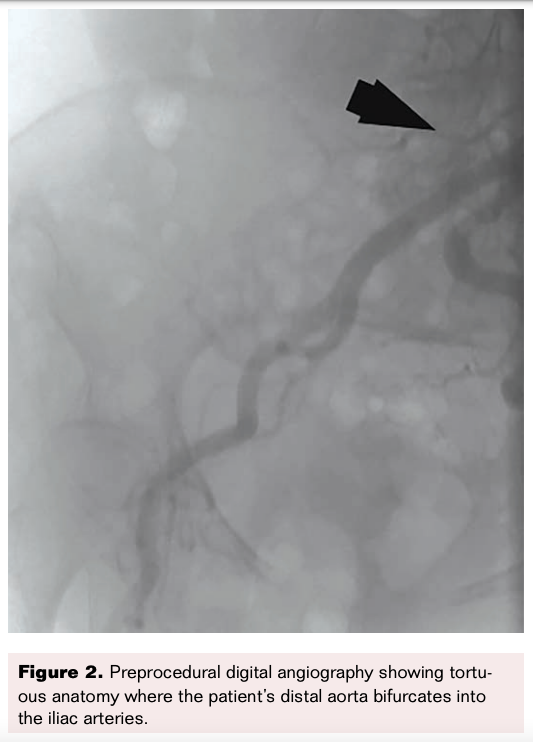

Based on prior angiography and experience during the previous atherectomy procedure, the patient was known to have unusually tortuous vascular anatomy, including a tortuous and calcified ascending aorta; highly angular, near-horizontal geometry at the distal aorta bifurcation into the iliac arteries; and a near 180-degree turn where the distal aorta transitioned to the right iliac artery (Figure 2).